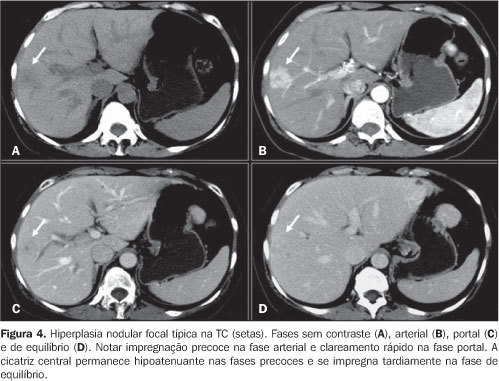

Hiperplasia Nodular Focal - TC